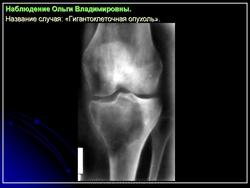

Обычно в пораженном метафизе располагается овальный очаг разрежения, кортикальный слой на его уровне истончен, кость «вздута». При небольшом распространении опухоль располагается несколько эксцентрично, а при обширном поражении — центрально.

При агрессивном течении процесса кортикальный слой истончается до толщины папиросной бумаги, а иногда разрушается. Остеопороз отсутствует. Структура очага крупноячеистая, а при литической форме однородно просветленная. Разрушения суставного хряща не наблюдается.

Рентгенологическое исследование гигантоклеточной опухоли показывает, что гигантоклеточиая опухоль локализуется в эпифизе и распространяется на метаэпифизарную часть кости. Поражение носит литический характер, имеет четкие контуры и умеренно или слабо контрастные костные балки. На границе метафиза контуры новообразования менее четкие, чем на остальном протяжении. Склеротические изменения вокруг опухоли развиваются редко, а такие угрожающие признаки, как козырек Кодмена или «лучистый венец», очень редки. Многие гигантоклеточные опухоли не выходят за пределы пораженной кости, но иногда они прорастают кортикальный слой и выходят в мягкие ткани, где покрываются тонким слоем новообразованной кости, едва заметкой при рентгенологическом исследовании. Такие же новообразования кости в виде «яичной скорлупы» имеются в имплантатах опухоли в мягких тканях и в метастазах в легких. Некоторые исследователи различают три стадии развития гигантоклеточной опухоли. На первой стадии узел небольшой, бессимптомный и не выходит за пределы пораженной кости. Вторая стадия документируется довольно объемным новообразованием, вплотную подходящим к наружному контуру кости. На третьей стадии опухоль проявляет агрессивные свойства и дает яркую клиническую симптоматику, связанную с се быстрым ростом и возникновением патологического перелома. На компьютерной томограмме отмечаются деструкция кортикального и медуллярного слоев и проникновение опухоли в окружающие мягкие ткани.